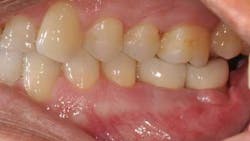

This patient presented with a missing No. 18 and hopeless No. 17 and No. 19 due to localized severe periodontal disease, recurring abscesses, and tooth migration. Severe bone loss can be seen on the initial periapical (Fig. 1) and panoramic (Fig. 2) radiographs.

The patient was treatment planned for removal of No. 17 and No. 19 and dental implant replacement for No. 18 and No. 19. Upon removal of the hopeless teeth, a severe vertical and horizontal ridge deficiency will be expected. Teeth No. 17 and No. 19 were removed, the area was thoroughly debrided of granulomatous tissue, and a soft-tissue allograft (perioderm – Dentsply/Tulsa Dental) was placed at the time of tooth removal in order to thicken the soft tissues in preparation for the vertical ridge augmentation procedure.